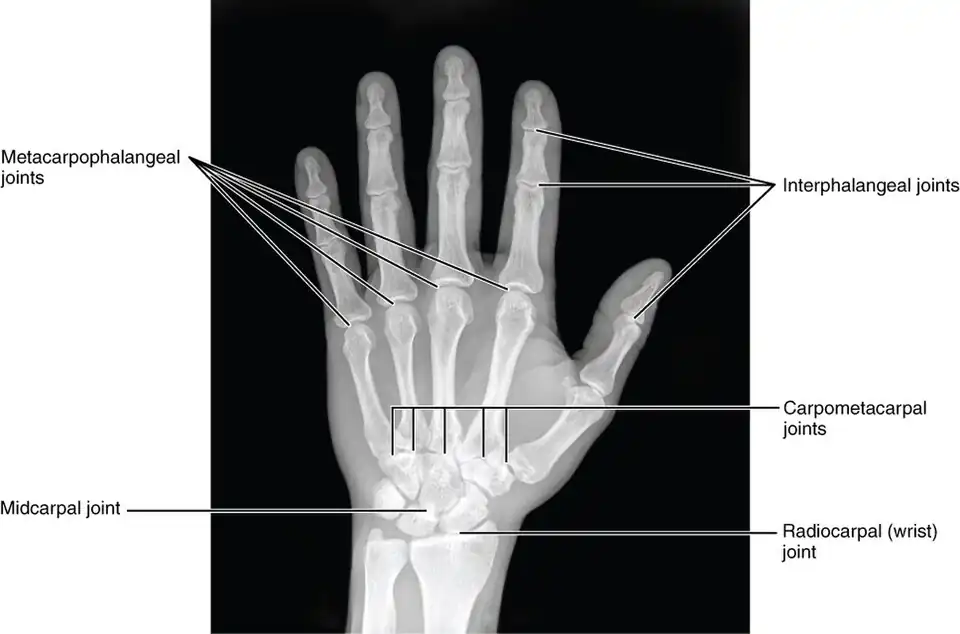

X-ray

X-ray image of right hand with thumb on left. -